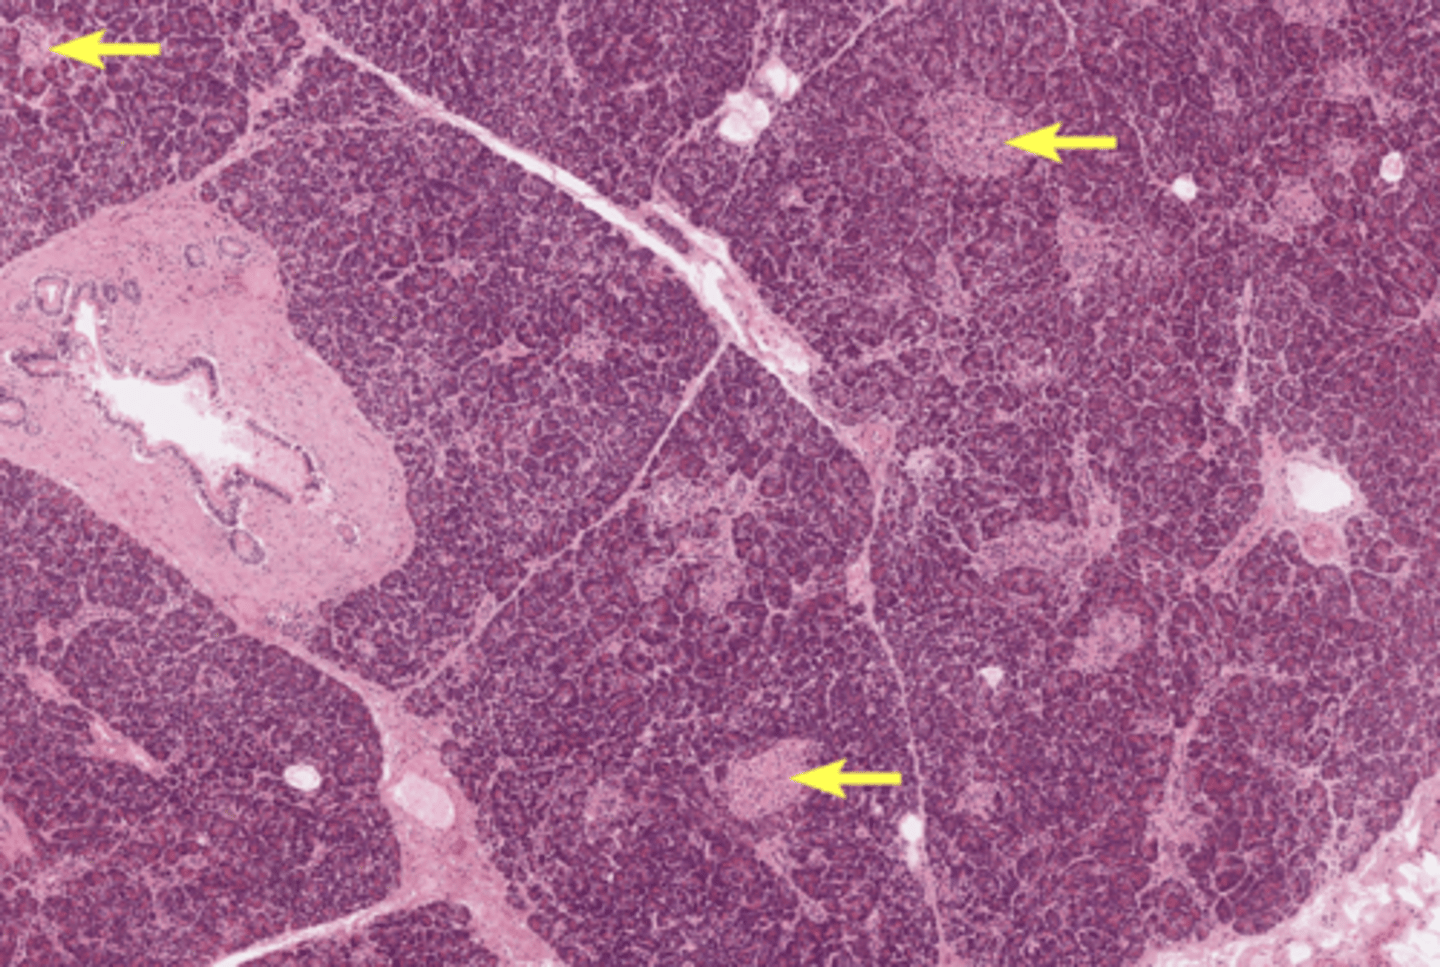

Pancreas

Pancreatic islet